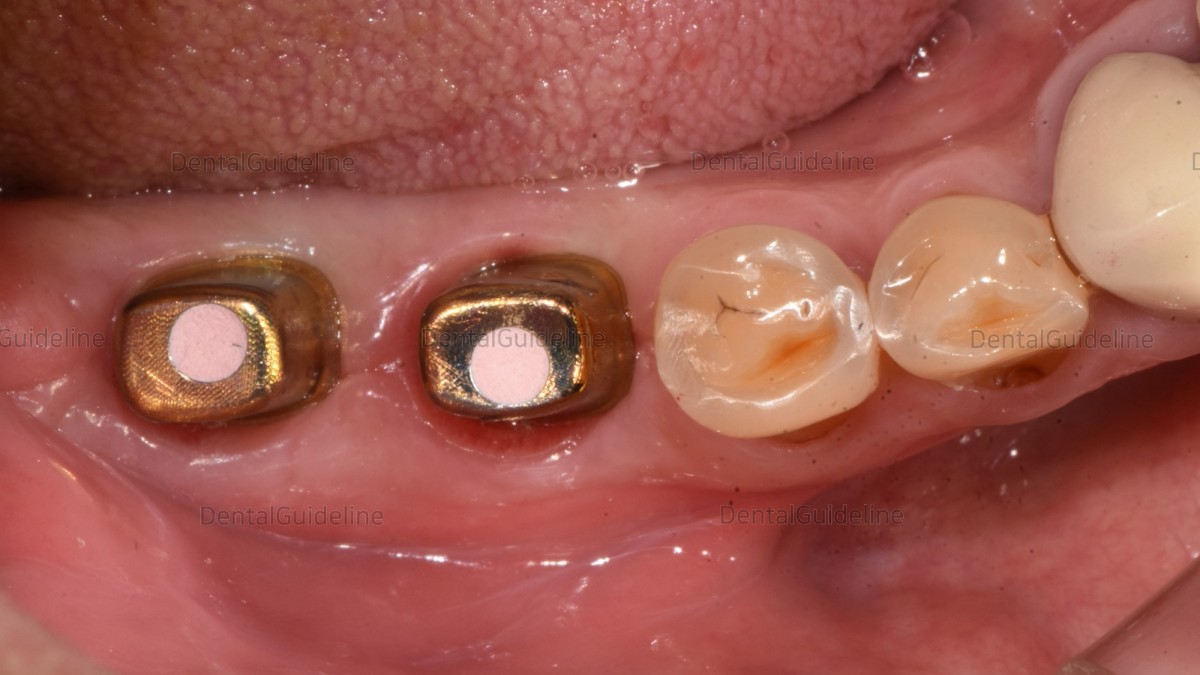

Initial view.

2months after extraction

After ISQ reading, Healing abutments were connected to the implants

Customized abutment and crown (zirconia)

abutment connection and screw hole filling

occlusal and contact point adjustment.

Permanent cementation and access hole filling with resin.